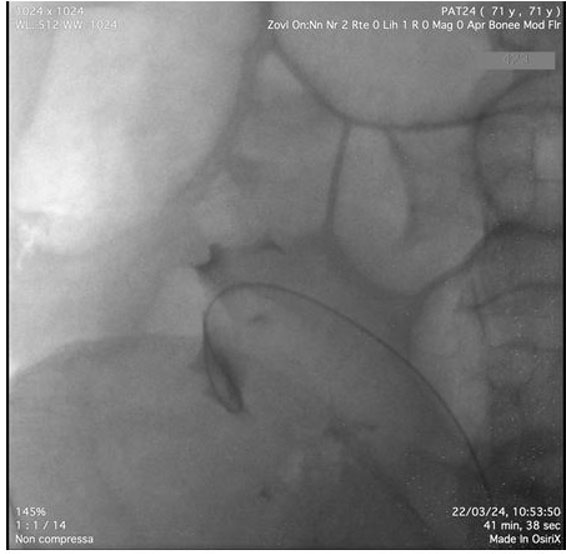

Pyelography was performed using an 8 Ch ureteroscope. After inserting the instrument into the bladder, the right ureteral meatus was identified and pyelography was performed with an open-ended catheter. The tortuosity of the ureter was confirmed, describing a double loop into the scrotum (Figure 2 and Figure 3). After identifying the renal pelvis, approximately in the right iliac fossa, a 6 Ch monoJ ureteral catheter was positioned.

Figure 3: Guidewire inside renal pelvis.